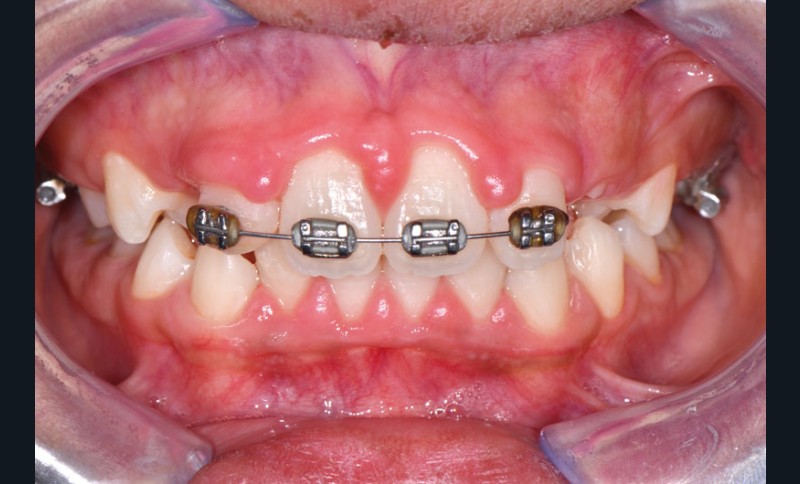

Ainsi, lors des périodes de désordres hormonaux, comme la puberté, la grossesse et la ménopause, on observe fréquemment des inflammations exacerbées qui peuvent révéler une susceptibilité de l’hôte aux maladies parodontales. (fig. 2 et 3).

Souvent, les signes cliniques régressent spontanément lorsque…